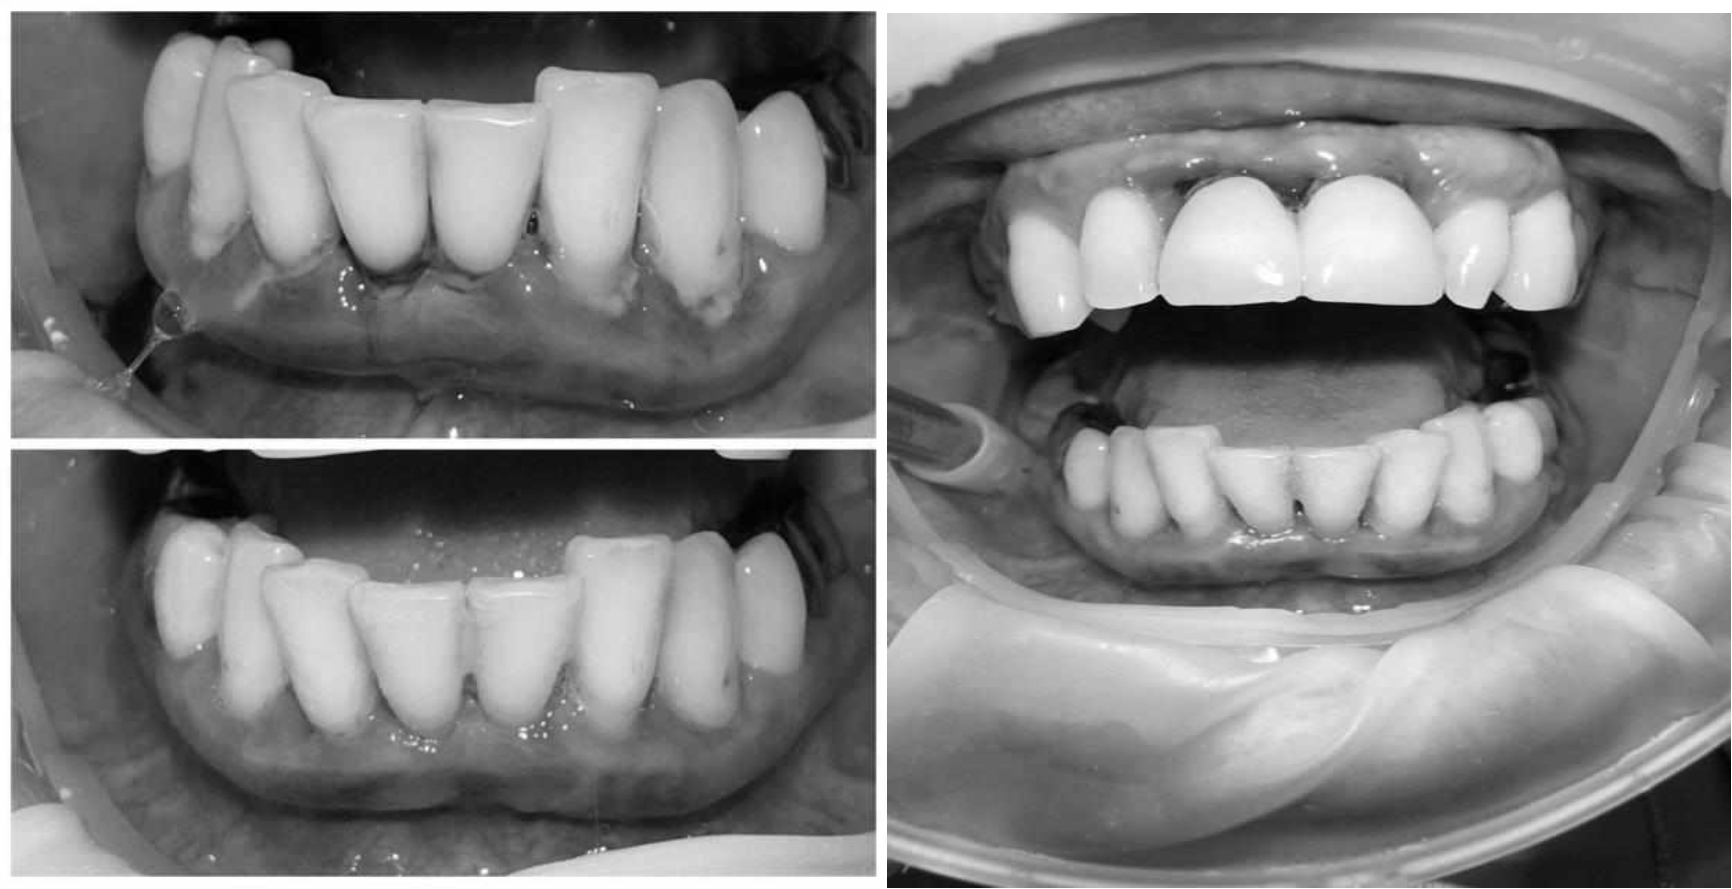

Ранее у пародонтолога не наблюдалась. При осмотре выявлены: неудовлетворительная индивидуальная гигиена полости рта, пародонтальные карманы до 7 мм, обильная кровоточивость и гноетечение из пародонтальных карманов, подвижность зубов 4.2, 4.1, 3.1, 3.2 II степени, обильные над- и поддесневые зубные отложения (рис. 1). На ортопантомограме отмечается резорбция костной ткани до ½ длины корня, очаги остеопороза (рис. 2). Пациенту был поставлен диагноз хронический генерализованный пародонтит тяжелой степени тяжести. При осмотре была составлена пародонтограмма с использованием компьютерного зондирования (рис. 3).

Рис. 2. Ортопантомограмма исходной ситуации пациента состояния полости рта